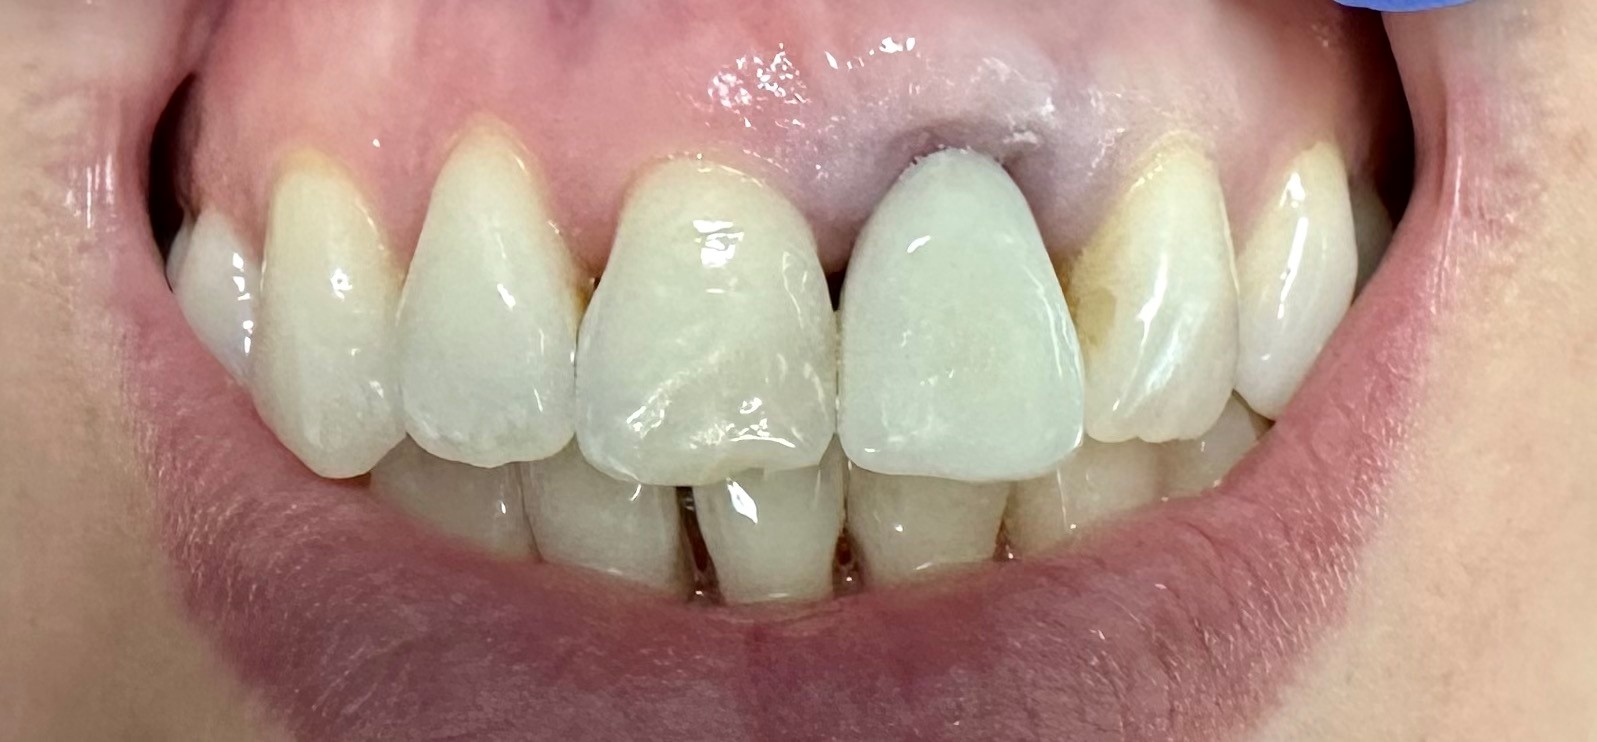

Widok w jamie ustnej przed usunięciem zęba (jedynka górna lewa) i wprowadzeniem implantu

Chirurgia: dr n.med. Ewa Zawiślak

Protetyka: dr n.med. Ewa Zawiślak